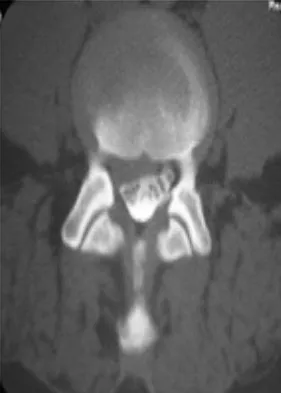

Which of the following choices best describes the fracture pattern shown in Figures 2a through 2c?

The fracture pattern shown in the radiographs is a fracture of the posterior column. The only line interrupted on the AP pelvis is the ilioischial line. The obturator oblique view shows that the iliopectineal line is intact as is the outline of the posterior wall. The iliac oblique view shows an interruption of the ilioischial line and an intact anterior wall. Therefore, this fracture is a fracture of the posterior column. Letournel E, Judet R: Fractures of the Acetabulum, ed 2. Berlin, Germany, Springer Verlag, 1993.

- Matta J: Surgical treatment of acetabular fractures, in Browner BD, Jupiter JB, Levine AM, et al (eds): Skeletal Trauma, ed 3. Philadelphia, PA, WB Saunders, 2003, vol 1, pp 1009-1149.